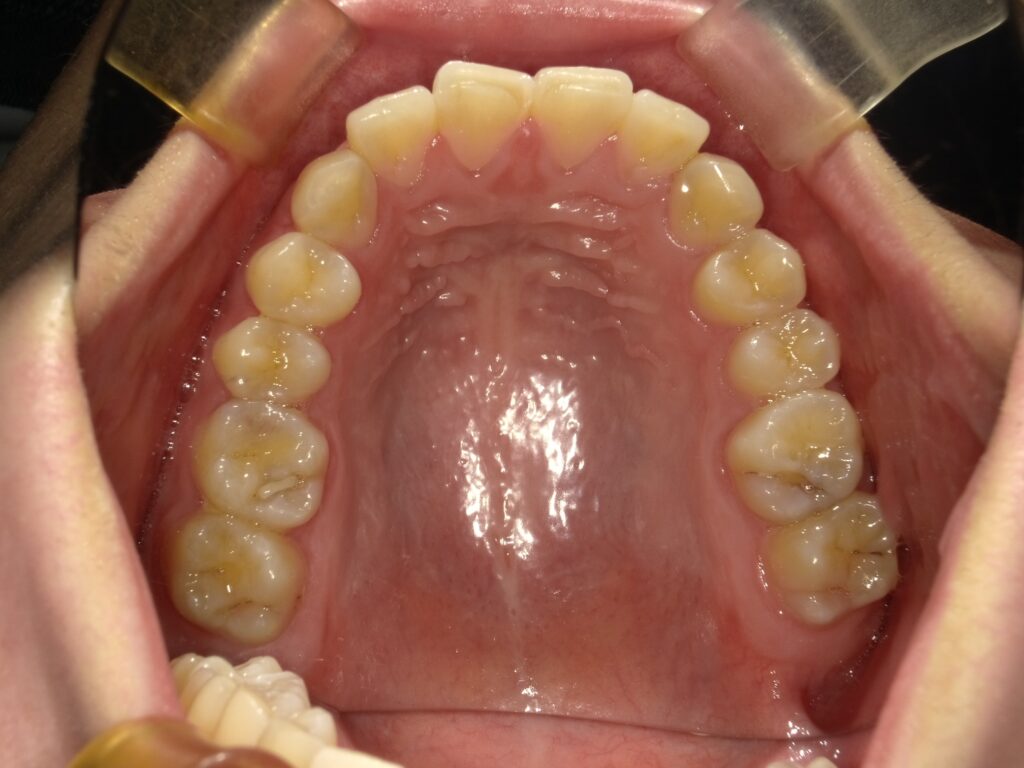

Before

部分矯正とは、気になる一部分だけを動かす矯正治療です。

特に多いのが「上の前歯だけ」「下の前歯だけ」というケースです。